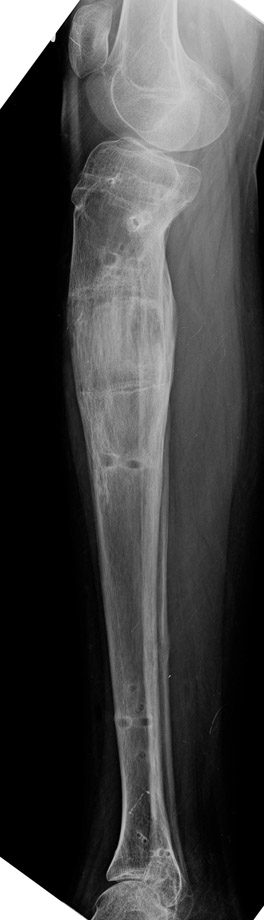

Travma Sonrası Bacak

Vaka 3